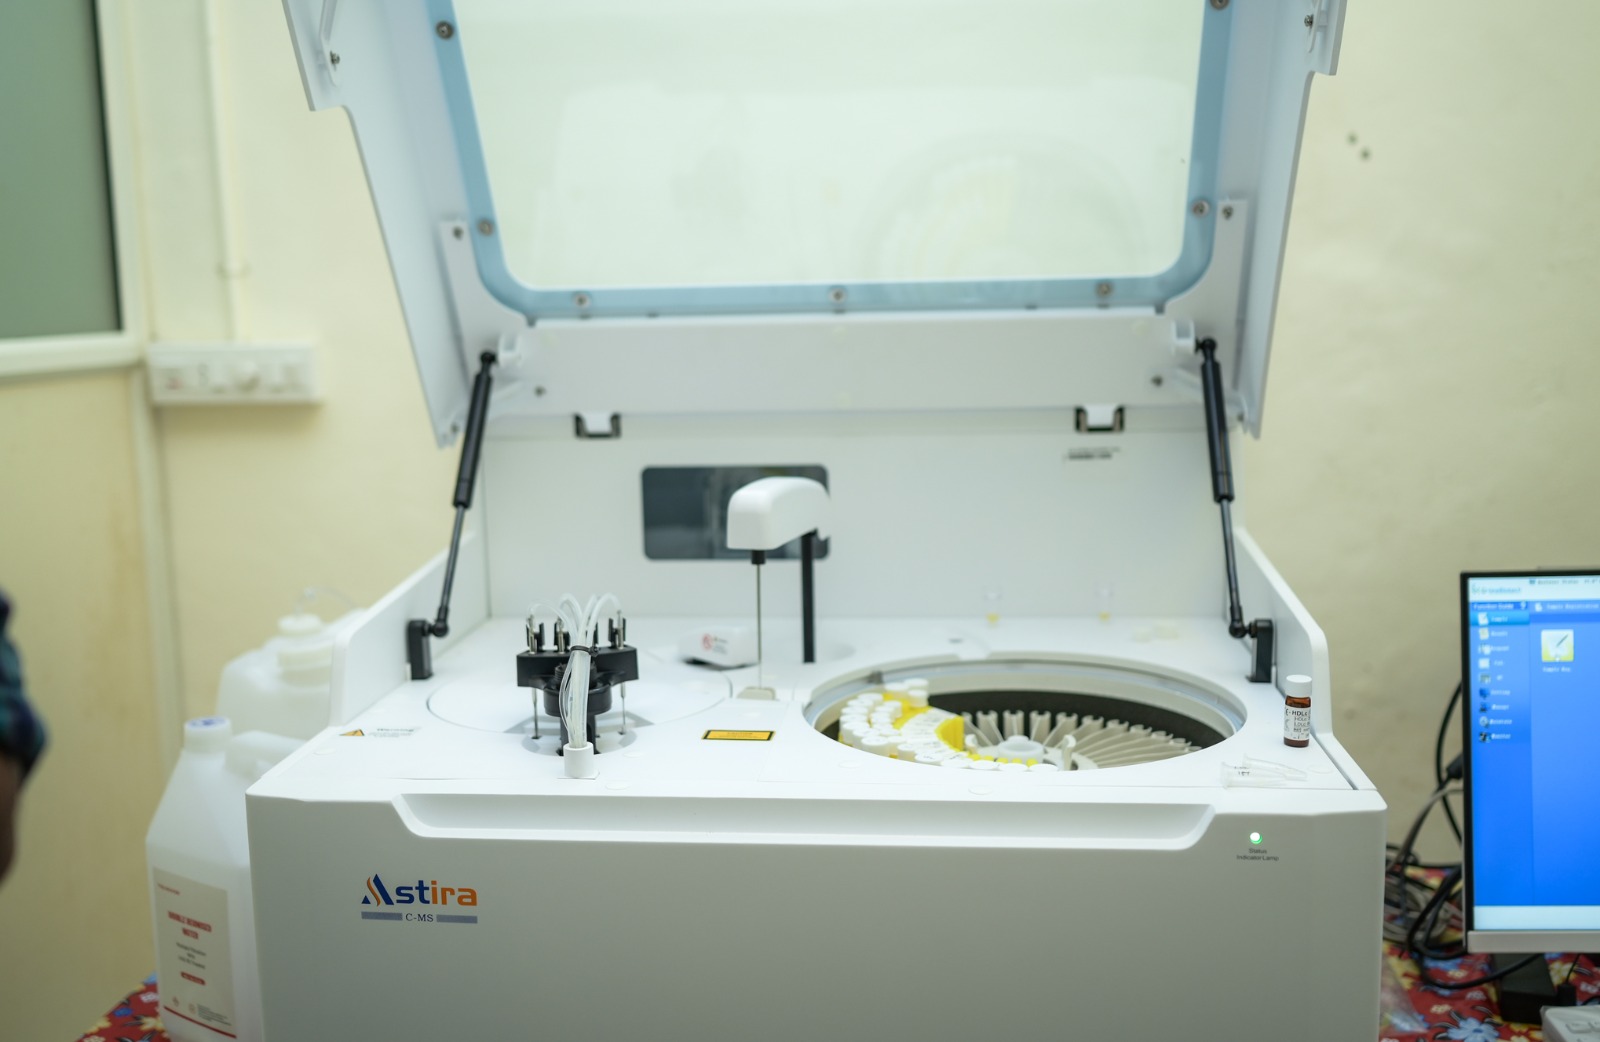

Our state-of-the-art Automated Diagnostics Lab is equipped with cutting-edge technology to deliver accurate and swift results. With advanced machinery and automated processes, we ensure the highest level of precision in diagnosing various health conditions

Rest assured that our lab's accreditation by the ALC (Accreditation of Laboratory Certification) ensures the highest standards of quality and reliability. We uphold stringent protocols and undergo regular evaluations to maintain this esteemed accreditation, providing you with trustworthy and accurate diagnostic results you can rely on

Discover a world of advanced medical testing at Aswas Diagnostics. Trust in our expertise for comprehensive and reliable healthcare solutions.